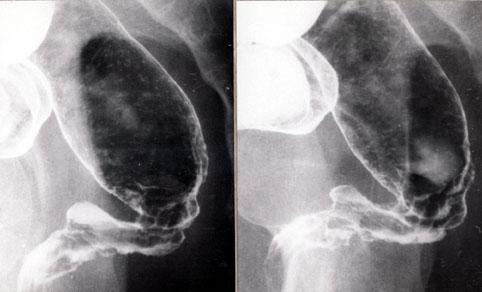

직장의 크론병예

염증성 및 궤양성질환/크론병

대장/직장

X-P

40이상